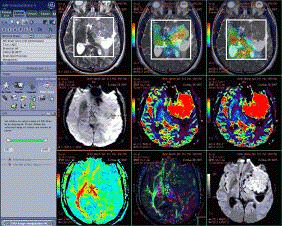

Визуализация с помощью Discovery MR750w 3.0T не похожа на то, что использовалось ранее. Посредством градиентов высокой производительности при коротком времени сканирования, неизменной четкости и однородности с использованием РЧ передатчика MultiDrive, а также большой области сканирования 50x50x50 см, Discovery MR750w предлагает бескомпромиссное покрытие и качество.

Визуализация без использования контрастного вещества - выполнение визуализации нижних конечностей при высоком разрешении и без использования контрастного вещества и с применением Inhance DeltaFlow, нейровизуализации артерий и вен с применением 3D PC Inhance, количественная визуализация перфузии с применением 3D ASL, а также непрерывная и надежная визуализация при свободном дыхании сети вен и артерий с применением IFIR. Все, без контрастного вещества.

Визуализация всего тела - выполнение визуализации всего тела без изменения положения пациента или катушек, проведение визуализации брюшной полости вне зависимости от дыхания с использованием PROPELLER

Скелетно - мышечная система - выполнение независимой от движения визуализации T1, T2 и PD для улучшения отображения таких тонких структур, как хрящи, мениск, связки и губы с использованием PROPELLER.